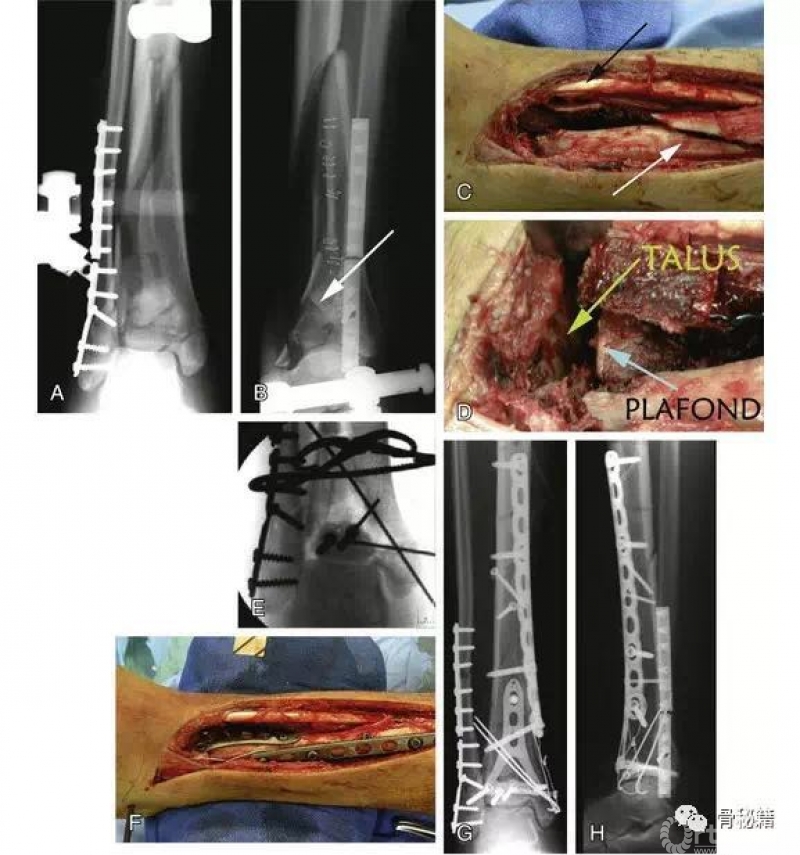

五、复杂pilon骨折的复位和内固定

A和B 腓骨钢板和跨关节外架的应用。注意关节面的压缩(箭头)。

C 前内侧切口。注意胫前肌腱(黑色箭头)和胫骨干骨折(白色箭头)。

D 关节面的复位。

E 使用克氏针复位,然后使用螺钉固定。

F 应用中和钢板。

G和H 术后轴和关节面的前后位X线片和侧位X线片。

一旦关节面重建后,应主要注意干骺端的交界处。当复位长骨骨折时,力线的对齐是主要的功能要求。与关节复位相反,干骺端重建的目标较少依赖于解剖复位,更多依赖于恢复足够的长度和旋转以及力线的对齐。这也可以通过使用外架或股骨牵引器来实现。